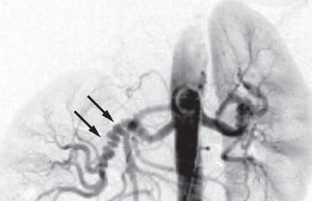

Lassiter, F. D. The string-of-beads sign. Radiology 206, 437–438 (1998).